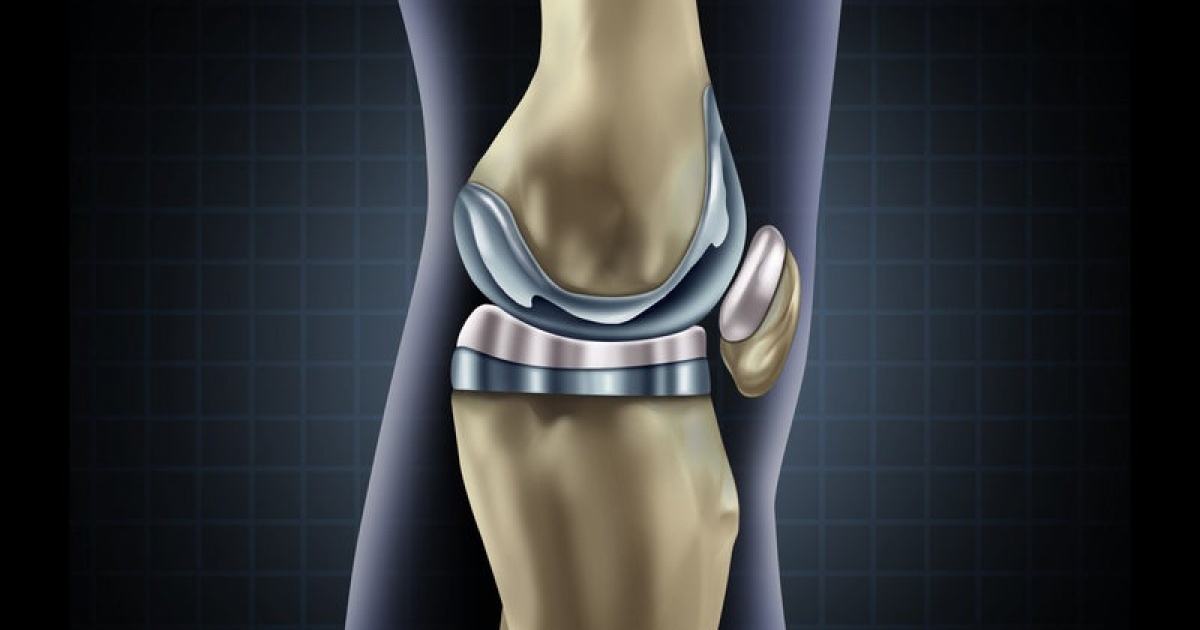

Фотографии и примеры протезирования коленного сустава